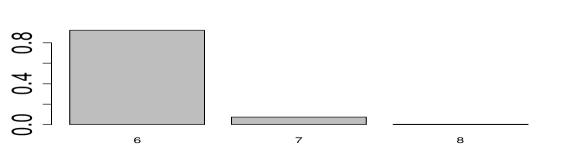

Inference summaries are reported in Figure 5. Figure 5(a) shows the posterior distribution of the number of latent diseases. The posterior mode occurs at the true value . Conditional on , the posterior point estimate is displayed in Figure 5(e) with mis-allocation rate 111The percentage is computed based on free parameters in only.. Conditional on , the point estimates and are provided in Figures 5(f) and 5(g). The similarity between the heatmaps of the simulation truth and estimates indicates an overall good recovery of the signal. The error rates in estimating and are 0% and 2%, respectively. We repeat this simulation 50 times. In 96% of the repeat simulations, we correctly identify the number of latent diseases; in the remaining 4%, it is overestimated by 1. When is correctly estimated, the average mis-allocation rate, error rates for and are 3%, 1% and 1% with standard deviation 0.5%, 1% and 1%, respectively. We provide addtional simulation studies in Supplementary Material A to investigate the performance of DFA with different hyperparameters and with the alternative prior that was introduced in (3).

We ran the MCMC algorithm described in Section 4 for 50,000 iterations. The first half of the iterations are discarded as burn-in and posterior samples are retained at every 5th iteration thereafter. Goodness-of-fit and MCMC convergence diagnostics show adequate fit and no evidence for lack of convergence (Supplementary Material B). Posterior probabilities for the number of latent diseases are and , respectively, i.e., the maximum a posteriori (MAP) estimate is . This includes the 4 a priori known diseases as well as 10 newly discovered latent diseases.